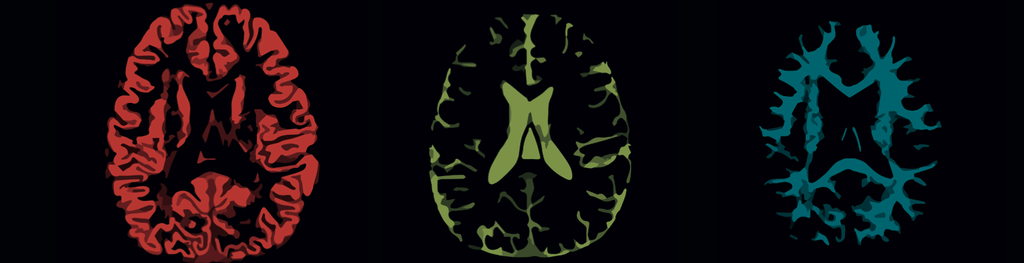

icometrix offers an FDA-cleared solution for the objective monitoring of patients with neurological disorders such as dementia, Multiple Sclerosis and epilepsy.

icometrix, founded in 2011, is an innovative company with headquarters located in Leuven, Belgium and, since 2016, a US office in Boston. Our goal is to bring quantitative MRI biomarkers from research to clinical practice.

icometrix is the global leader in MRI biomarkers for routine clinical practice, which analyzed over 10,000 clinical scans worldwide. The recent FDA clearance allows us to expand this success to the US.